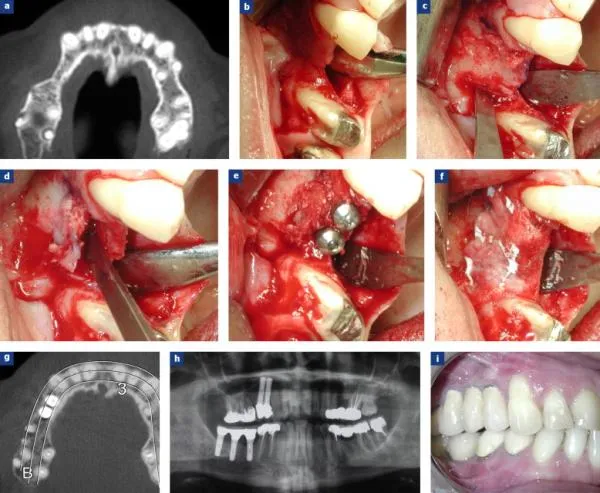

- La chirurgie pré-implantaire massive

(greffes osseuses d’origine calvariale ou iliaque)